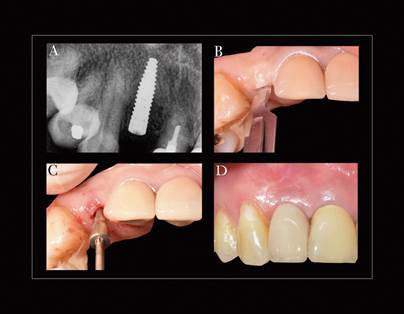

Luego de 6 meses se procedió con la cirugía de conexión, se realizó una incisión lineal supracrestal sin tocar las papilas adyacentes con un elevador micro Buser, se levantó un pequeño colgajo de espesor total en el cual se expuso la tapa de cierre del implante, la cual fue retirada y mediante una técnica de expansión se puso un pilar de cicatrización de 3.5 mm de altura y 3.6 mm de conicidad. Luego de 2 minutos de expansión se retiró el pilar de cicatrización y se cambió por un pilar provisorio de Corona Tam Straumann® (Basilea, Suiza) y se personalizó el perfil de emergencia con Resina Flow según los principios de Su H. y cols.6. Simultáneamente a la cirugía de conexión, se tomó una biopsia de tejido mucoso tomando epitelio y conectivo, mediante una incisión supracrestal paralela a la incisión de la conexión, la muestra fue sometida posteriormente a un estudio histopatológico. Antes de comenzar la rehabilitación se realizó una radiografía retroalveolar de control, la cual confirmó la preservación alveolar, ya que el implante presenta una posición apicoronal yuxtaósea, además la imágen confirma la eliminación del proceso apical (Figura 6).

En el presente reporte los resultados clínicos de la utilización de un xenoinjerto como relleno óseo y de una matriz colágena de origen porcino dieron como resultado la preservación alveolar, lo cual se confirmó mediante un control radiográfico el cual demostró la eliminación de la lesión apical preexistente y la mantención del nivel óseo, ya que el implante mantuvo el nivel yuxtaóseo de posicionamiento inicial. Además de una regeneración completa de tejido blando. Los resultados clínicos variaron desde un puntaje de 0 para la primera semana de control, en donde estuvo marcado por un ancho mayor a 2 mm de herida, una depresión en la zona central, un enrojecimiento de la zona quirúrgica, marcas de las suturas y una pobre apariencia estética inicial, a un puntaje final de 5 a los 6 meses, según la escala de evaluación de cicatriz Stony Brook7, con una apariencia estética final óptima del tejido regenerado.